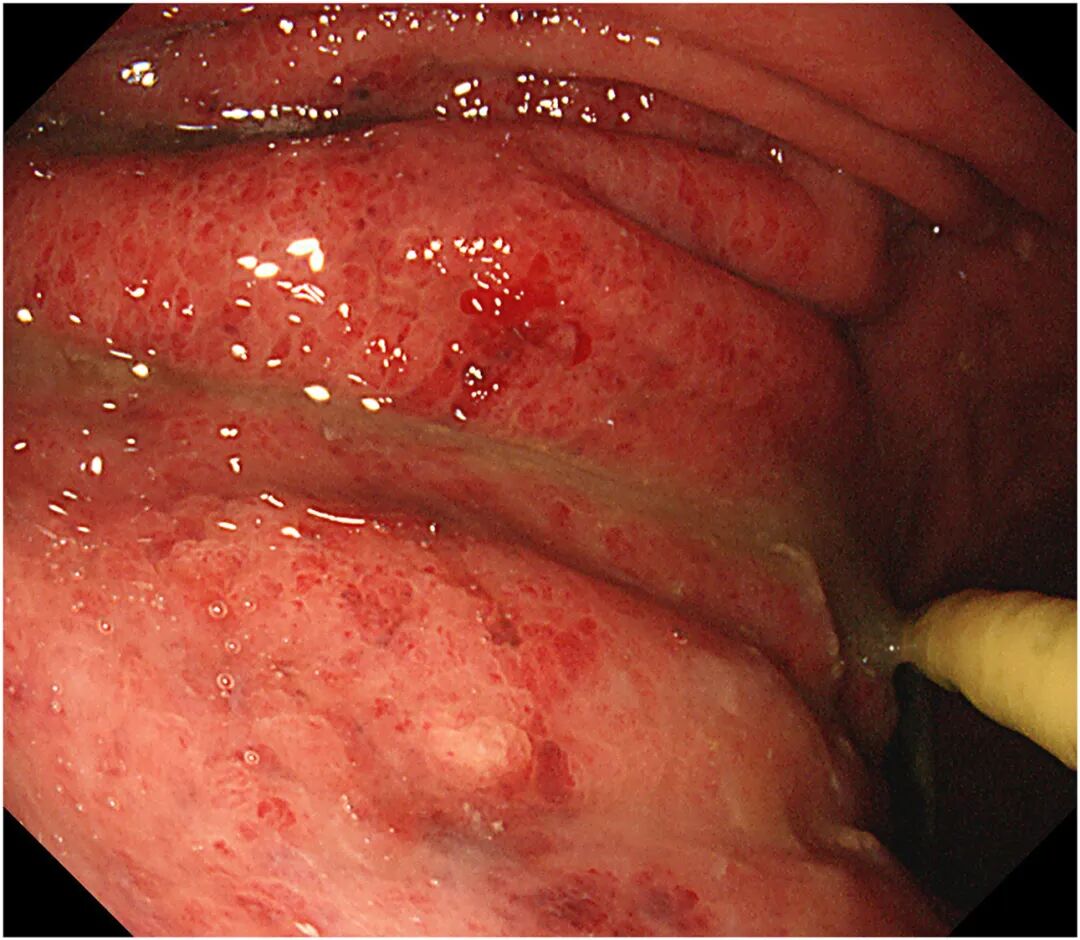

行上消化道内镜检查显示,胃体、胃大弯及前壁黏膜充血

图5 上消化道内镜显示